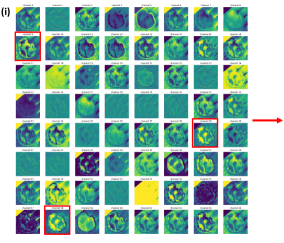

Figure 2a. illustrates the information retrieved from this CNN model from various layers of the architecture that is used to create a BAM map, which is used to segment the burn injury from normal skin in a 2D image. First, the heatmaps for the activations of the first convolutional layer are computed (Figure 2a(ii)), and then Grad-CAM heatmap is computed using the last convolutional layer (Figure 2a(iii)). Once the first convolutional layer heatmaps and Grad-CAM are generated, the algorithm uses a three-round iterative process to select activation heatmaps that have the highest correlation to the Grad-CAM heatmap among the channels of the first layer activations. After the process of correlating and selecting heatmaps is completed (Figure 3 ), segmentation masks are created next (Figure 4). A final composite BAM mask is created as illustrated in 2b(i). Finally, figure 2b (ii-iii) illustrates how the BAM mask is superimposed on the input image to segment the burn injury area, and how edge detection may be applied to the BAM mask in order to obtain a fine-tuned segmented boundary superimposed on the input image.

Figure 3 and Algorithm 1 detail the iterative process that is used to select the activation channel heatmaps and Grad-CAM, by the algorithm. For the example burn image, the first iteration of the algorithm selects channel since it has the highest correlation to the Grad-CAM heatmap among the channels of the first layer activations, as given by the Spearman’s correlation coefficient, . The second iteration selects channel to be added to the combination since averaging it with channel results in the highest increase in the correlation value with the Grad-CAM heatmap. Finally, the third iteration adds channel to the combination of channels and .